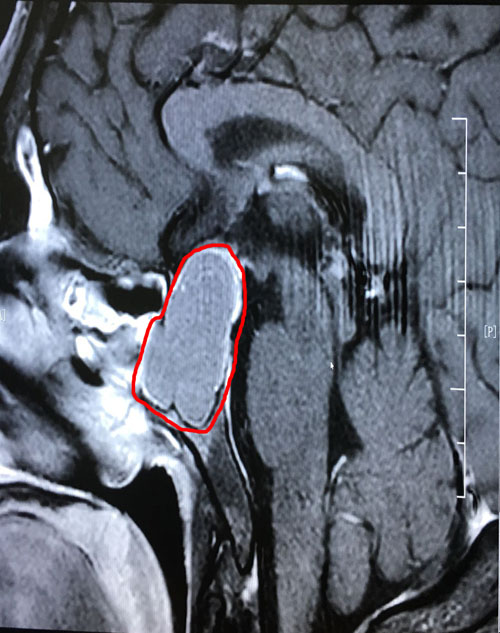

术前影像显示:垂体巨大腺瘤,突破鞍隔向上生长

到院后,李士其教授和潘仁龙主任一起,研究讨论了患者病情:由于患者颅内鞍区的肿瘤很大(约1.8*3.1公分),已严重影响到患者的垂体功能,并压迫视神经,感觉神经等功能。李士其教授表示:手术是刻不容缓的事,待患者检查结果出来,没有手术禁忌,就可以立即实施手术。